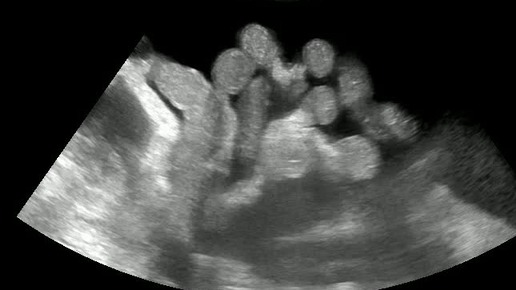

Видео к статье: "Свободная жидкость в брюшной полости"https://dzen.ru/a/Z-1KdOK-KyrjRiGF

Ультразвуковые находки от врача УЗД Зорина Я.П.